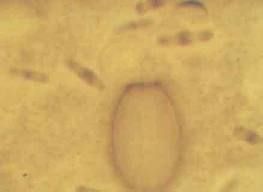

雙芽焦蟲病是由雙芽焦蟲引起的急性病。黃牛、水牛等放牧牛容易感染。多發生在夏、秋季,1歲以下牛發病率高,但表現症狀較輕,死亡率低;7成年牛感染率低,但死亡率高。良種牛、引進牛很容易感染,發病也重。巴貝斯焦蟲病是由巴貝斯焦蟲引起的急性病。多發生於夏秋季節,成年牛表現症狀較輕,l歲以內的牛發病多、病情重、死亡率高,耐過或治療過的牛成為帶蟲者。

體溫40~41.5°C,貧血,黃疸症狀明顯,血尿,體表淋巴結腫大。病死牛的皮下組織黃染,血液稀薄,脾臟腫大。雙芽焦蟲病和巴貝斯焦蟲病有血尿,剖檢時尿液紅色。泰勒焦蟲病無血尿症狀。